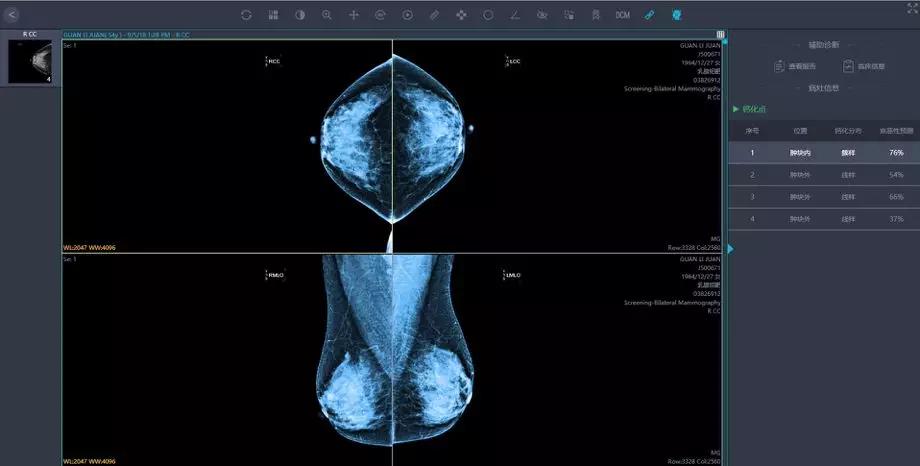

將這些影像學及臨床資料匯集,就為人工智能技術提供了大數(shù)據(jù)基礎。人工智能的影像識別和深度學習能力,能夠幫助醫(yī)生篩除正常影像,著重標注疑似病灶的區(qū)域,讓影像科醫(yī)生審片更加精準高效。

人工智能在影像識別的速度上勝于人工操作,同時也有利于臨床醫(yī)生制定針對性的治療方案, 特別對于偏遠地區(qū)和基層醫(yī)生而言,這一技術的應用更加意義重大。

人工智能技術可以進行多模態(tài)影像數(shù)據(jù)融合,多維度,立體化進行數(shù)據(jù)融合分析,為乳腺癌的診斷及治療提供全面的個體化的綜合信息。

針對來自多個醫(yī)療中心的海量影像數(shù)據(jù),英特爾至強服務器提供最高達768GB的超大內(nèi)存,配合多核心多線程處理能力,對乳腺采集影像進行像素級別的特征識別,在紛紛擾擾的世界中尋找蛛絲馬跡,發(fā)現(xiàn)潛在問題。

數(shù)據(jù)識別更加精準

匯醫(yī)慧影公司曾在胸部結(jié)節(jié),神經(jīng)系統(tǒng),甲狀腺等多器官系統(tǒng)影像與國內(nèi)外頂級醫(yī)院的影像及專科醫(yī)生進行過人機讀片對比,經(jīng)過深度學習的人工智能系統(tǒng),讀片準確率達到90%。

英特爾至強服務器可將深度網(wǎng)絡模型優(yōu)化并將數(shù)據(jù)集進一步加強,也將會繼續(xù)幫助提高該識別準確率,其對數(shù)據(jù)的分析和比較“眼力”,早已突破人類極限,達到醫(yī)療影像辨識的新高度。